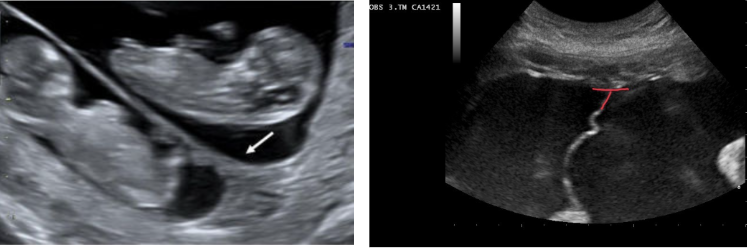

Results from arteriovenous communication between the circulatory systems of monochorionic twins (10-15%) Recipient twin becomes hypervolemic, large for GA, produces excessive urine leading to hydramnios, heart working hard to pump extra blood (can lead to heart failure) Donor twin hypovolemic, leading to severe, generally symmetric growth restriction, produces little urine resulting in oligohydramnios; “stuck-twin” Prognosis is poor for both twins

Twin Transfusion Syndrome

Monochorionicity Marked discordance in AFV Discordance in size Larger twin in hydramniotic sac, large bladder, possibly hydropic with enlarged heart Smaller twin in oligohydramniotic sac, bladder NWV – “stuck-twin” Check cord Dopplers (🡩 RI?, 🡫, absent, or reversed end-diastolic flow?)

40

twin transfusion syndrome can be suspected when one twin is at least _____________ larger than the other.

25%